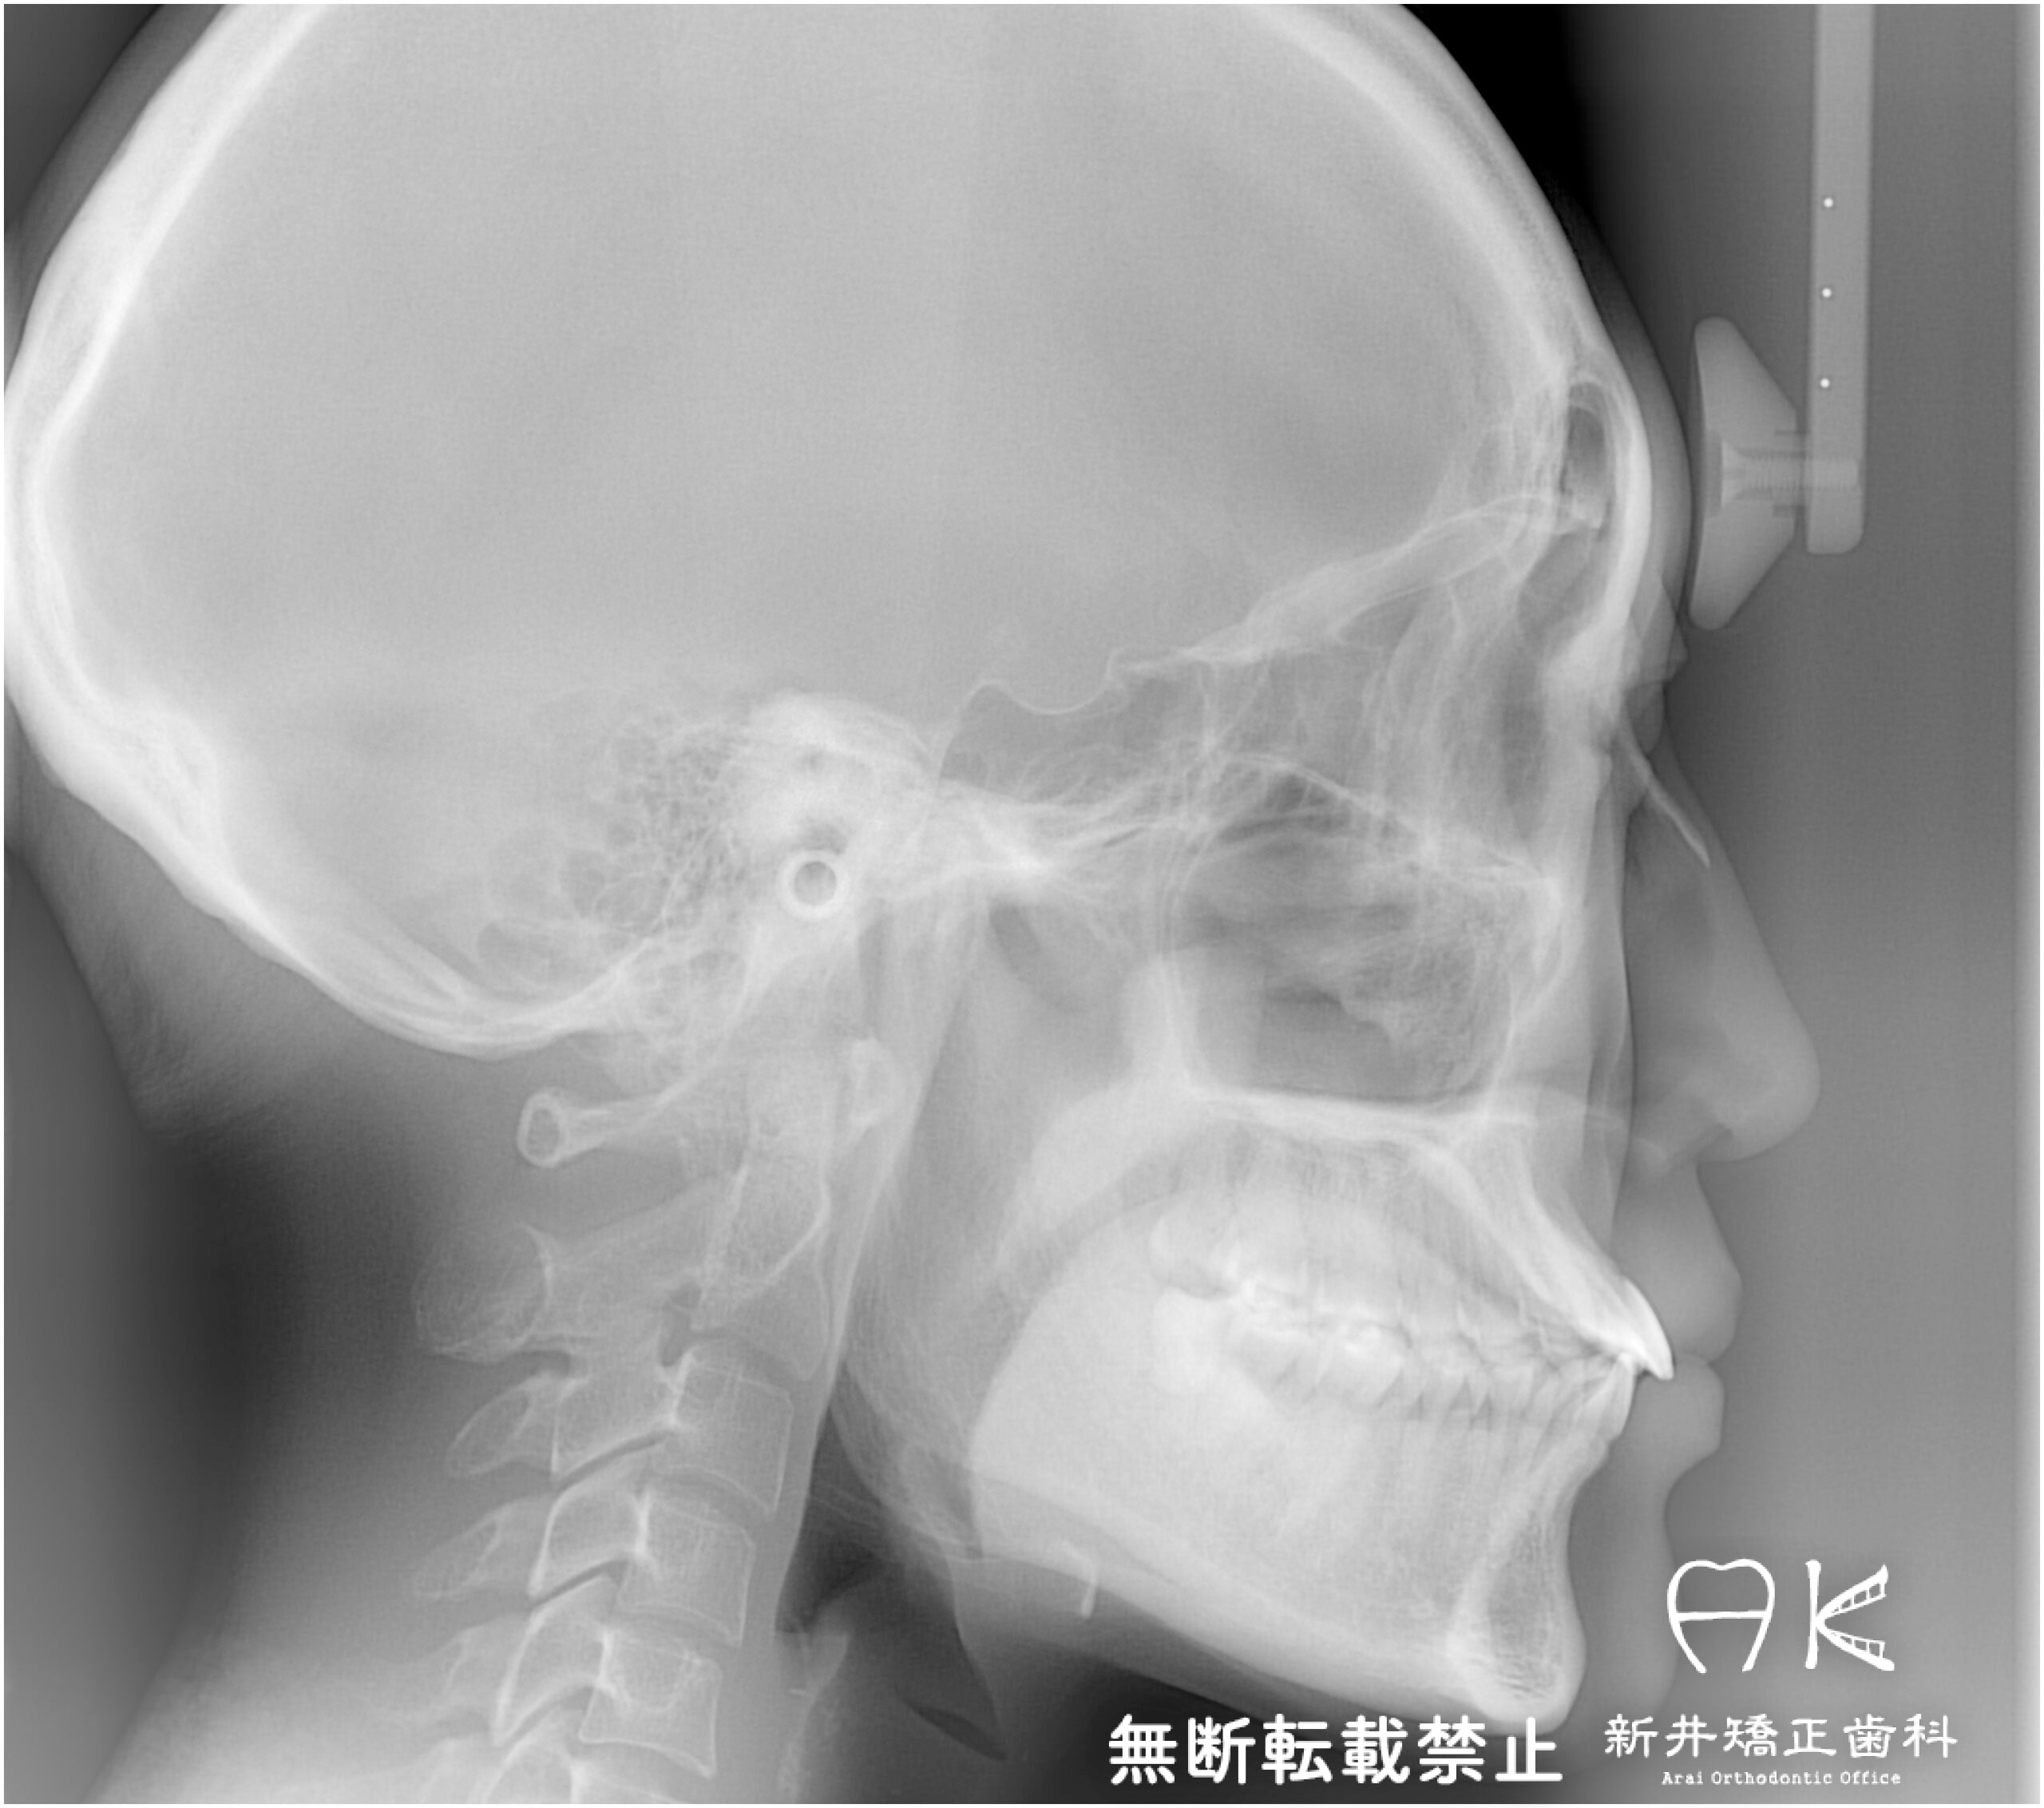

セファログラムのトレースの重ね合わせ(緑:治療前、赤:治療終了時)

治療前後の解説

| 治療前 | でこぼこしている歯による歯磨きのやりにくさや、奥歯がしっかり咬んでいない鋏状咬合(すれ違い咬合)。 出っ歯による口の閉じにくさ(口唇閉鎖不全)と、正面から見た時のオトガイ部にできる梅干し様のシワやイーラインから飛び出た口元(口ゴボ)。 機能面も審美面も気にしていた患者さんです。 治療中もなるべく装置を目立たせたくないため、ハーフリンガルでの治療となりました。 |

|---|---|

| 治療後 | 上下の歯がお互いにはまり込み、全体的に緊密な咬み合わせになっています。 出っ歯が治り、口元の突出感が改善されて綺麗なEラインを獲得しました。 すれ違い咬合や叢生(歯のでこぼこ)も治って歯磨きがしやすく、嚙みやすい状態になっています。 |